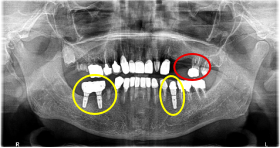

Before

※赤丸を抜歯しました。

After

※赤丸は、歯根が破折していたため抜歯しました

※黄色丸は、2006年10月に埋入したインプラント

※緑丸は、今回埋入したインプラント